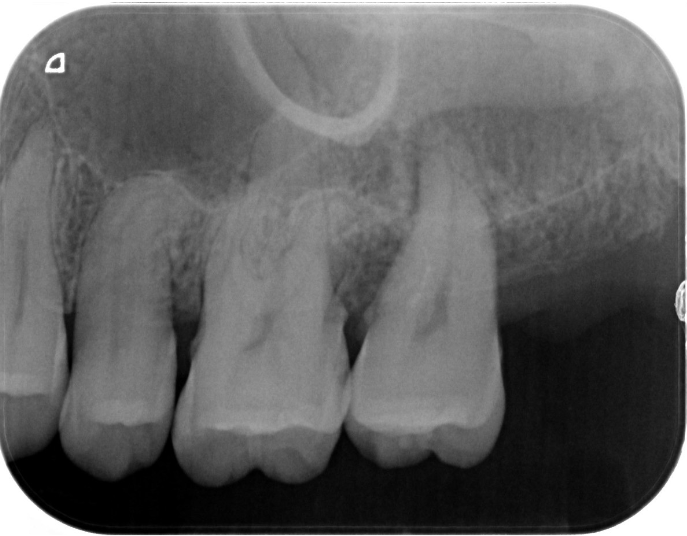

症例2

| 項目 | 詳細 |

|---|---|

| 患者様データ | 67歳 女性 |

| 来院時の主訴 | 「歯周病を治して一生自分の歯で食事を摂りたい。」 |

| 医院の診断 | 重度歯周病とう蝕 |

| 通院期間 |

1年6ヶ月 |

| 来院回数 | 10回 |

| 治療費 | 総額:480,000円(税抜) 歯周基本治療は保険適用診療 【内訳】 《保険適用診療》 歯周病検査・歯磨きや生活習慣指導・歯石取りクリーニング 《自費診療》 歯周組織再生療法240,000円(費用は範囲によって異なります。)、セラミック治療120,000円×2 |

| リスクと副作用 | メインテナンスが必要、正しい歯磨き習慣が必要不可欠 |

| ここがこだわりのポイント!☝ | 重度の歯周病の治療には長い治療期間がかかります。重症になるまでに時間がかかっている分、治るのにも時間がかかるからです。この症例の場合、患者様に頑張っていただいた結果、歯周ポケットが8mm→2mmに改善し、健康な歯周組織(骨・歯肉)を獲得することができました。 一生涯自分の歯で食事ができるよう、引き続きサポートを続けさせて頂きます!本当によく頑張って下さいました。お疲れ様でした! |